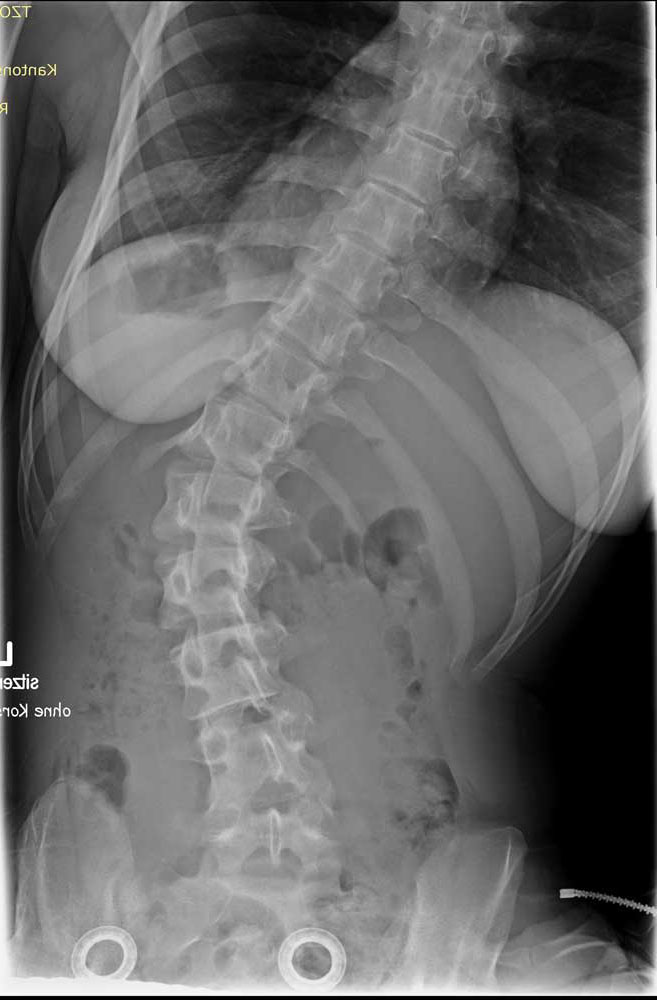

Standardisierte anterior-posteriore (a.-p.) Röntgenbilder wurden retrospektiv ausgewertet. Die Aufnahmen wurden bei allen Patienten in sitzender Position durchgeführt. Bei 3 Patienten wurden Röntgenbilder in stehender Position angefertigt. In liegender Position angefertigte Röntgenbilder waren nicht zulässig, da das maximale Ausmaß der Verkrümmung in dieser Position durch die fehlende Schwerkraft nicht sichtbar ist. Anhand der a.-p. Röntgenbilder wurden der Apex sowie die lumbalen und thorakalen Cobb-Winkel berechnet. Alle Winkel wurden mittels „Centricity Dicom Viewer V3.1“ gemessen. Bei demselben Krankenhaustermin wurden zwei Röntgenbilder angefertigt: eine erste Röntgenaufnahme (T1) mit Doppelschalenkorsett und nach 5 Minuten (T0) ein zweites Röntgenbild ohne Korsett. Dies war allerdings nur bei Patienten mit korrekter Anpassung des Doppelschalenkorsetts möglich. Bei den anderen Patienten betrug die Zeitspanne zwischen T1 und T0 nicht mehr als 3 Monate aufgrund notwendiger Anpassungen des Doppelschalenkorsetts durch den Orthopädietechniker. Der Grad der Korrektur des Cobb-Winkels im Bereich der Lenden- und Brustwirbelsäule wurde in Prozent des Messergebnisses ohne Korsett bei T0 ausgedrückt (Abb. 1 u. 2).

Die Abbildungen 3 und 4 zeigen die klinischen und radiologischen Befunde für eine 18-jährige Frau (Fall 17). In Abbildung 3 sind die klinischen Fotos ohne und mit Doppelschalenkorsett zu sehen. Abbildung 4 zeigt die Röntgenbilder dieser Patientin ohne (a) und mit (b) Doppelschalenkorsett.